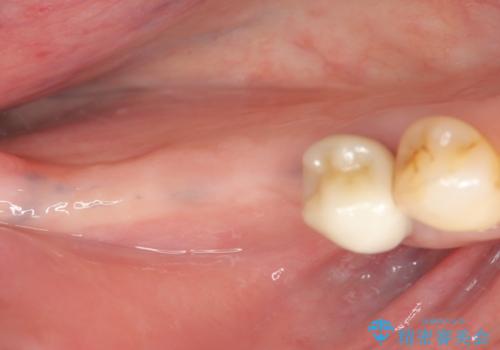

骨の造成を同時に行うインプラント治療

- 「長年使ってきた歯を失い入れ歯を入れてみたがよく噛めない、インプラント治療を受けたい。」とインプラントt利用を希望され来院されました。

骨は薄くなってしまい、インプラントの長期的な安定を見込むには不十分でしたのでインプラントの埋入と同時に周囲にコツの造成を行う治療計画を立てます。